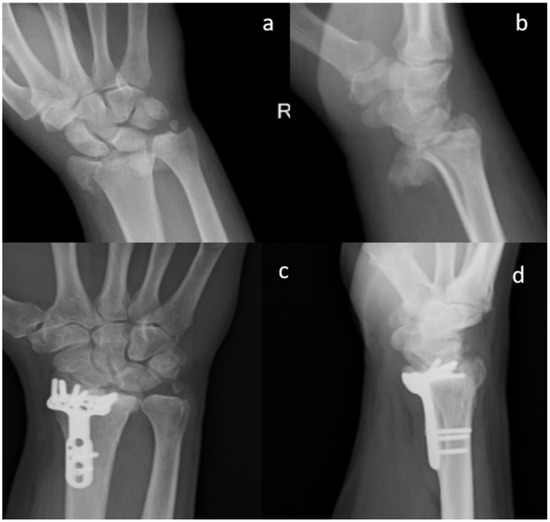

Figure 3.

Standard X-ray of a displaced articular fracture of the distal radius associated with styloid ulna fracture. Preoperative images in AP (a) and Lateral (b) view are compared to post-operative X Ray at five months (c,d). The images show callus formation and remodeling of the smart bone. (Male, 50 yy).